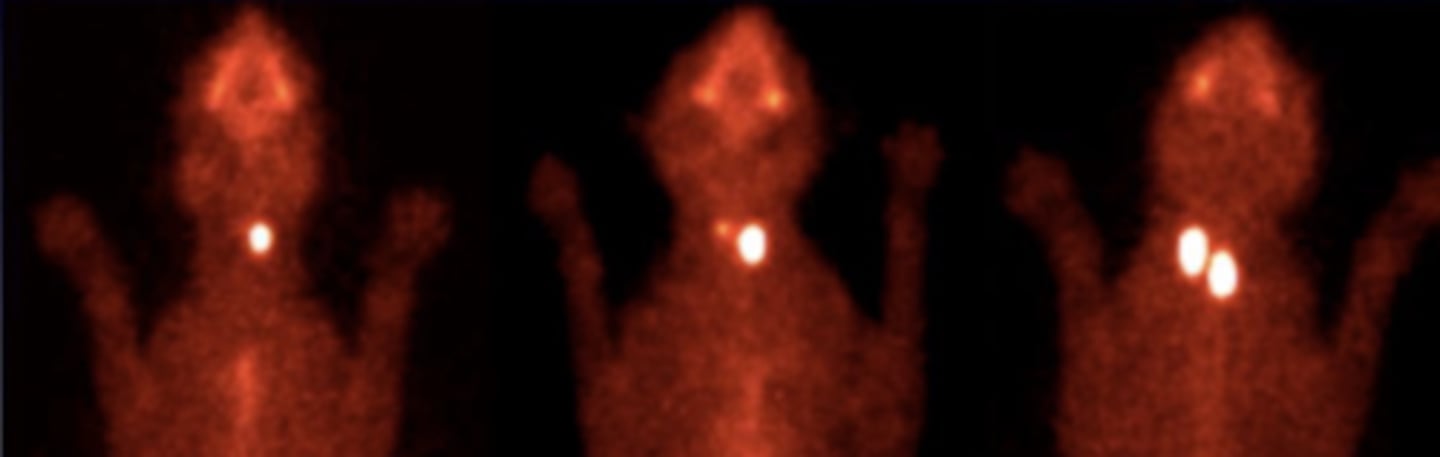

administering small amounts of radioactive materials, known as radioisotopes or radiotracers, via injection into the bloodstream, swallowing, or inhalation. They accumulate in specific organs or tissues in the body. The radiation emitted by these materials is detected by a gamma camera. it is used for detecting the functionality of specific tissues/organs

what is nuclear medicine?

nuclear medicine+ gammagraphy

what type of imaging is used to detect the functionality of different tissues/organs?

nuclear medicine+ gammagraphy

what type of imaging was used to produce these images?